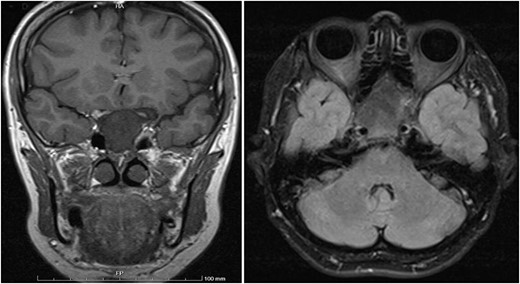

A 56-year-old female presented with a 1-year history of intermittent headaches, which had been increasing in severity and intensity over the last 2 months. The headache was mainly in the right parietal region, throbbing in nature and did not display diurnal variation. The severity of the headache was stated as 7–8 degrees on the Numerical Rating Pain Scale (NRPS; [6]). The pain was partially relieved with analgesia (acetominophen and ibuprofen). She also complained of mild right nasal congestion and intermittent mild otalgia. Physical examination was normal apart from nasal septal deviation. Computed tomography (CT) of the paranasal sinuses showed expansion of the sphenoid bone demonstrating diffuse ground-glass matrix and sclerosis obliterating the sphenoid sinus cavity (Fig. 1). Magnetic resonance imaging (MRI) was highly suggestive of fibrous dysplasia of the sphenoid bone, which appeared as expanded mass with dark T2 signal and T1 hypointense signal (Figs 2 and 3). Near-total excisional biopsy was performed using endoscopic transeptal approach to sphenoid sinuses. Histopathological examination of several pieces of greyish tan and brown bony tissue measuring 3.5 × 2.5 × 1.7 cm. showed branching irregular trabeculae of woven bone with intervening hypocellular fibrous stroma, consistent with a diagnosis of FD (Fig. 4). The patient’s headaches improved greatly following surgery. Two years post-op she reports infrequent headache with a severity of 2 on NRPS.

Coronal T1 image showing the expansion of the clivus with heterogeneous predominantly low T1 signal. Axial flair images showing the anteroposterior (AP) extension of the mass lesion with obliteration of the sphenoid sinuses. The cavernous portions of both internal carotid arteries (ICAs) have signal void intensity suggesting patency.